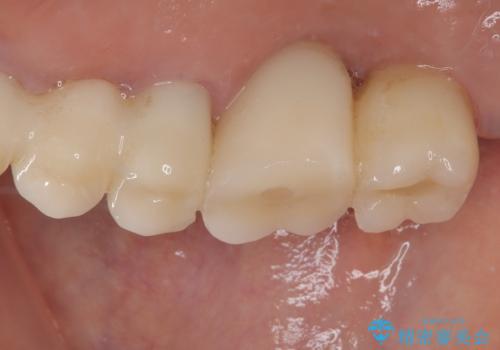

抜けてしまった奥歯 短期間インプラント治療

- インプラントが脱落してしまったとのことで来院された患者様です。

歯肉は綺麗に治癒しており、インプラント埋入に十分な骨があったため、速やかにインプラント埋入を行うこととしました。

インプラント埋入の状態が良ければ即日で仮歯を装着し、十分な生着が確認され次第、オールセラミッククラウンにて補綴治療を行うこととしました。

インプラントの初期固定も埋入後の生着もスムーズであったので、埋入から3ヶ月で無事に治療を終えることができました。